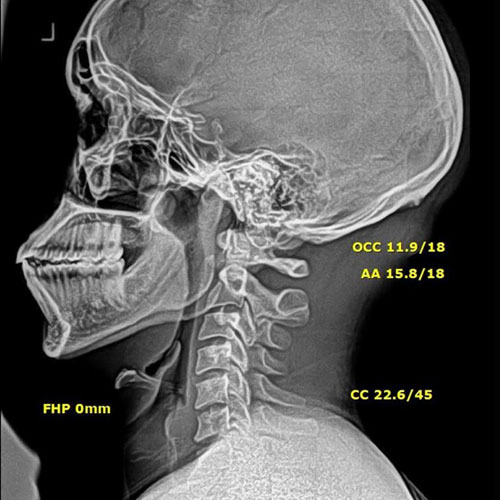

After Corrective Chiropractic Care: Following a customized course of corrective chiropractic treatment, repeat X-rays demonstrated measurable improvement in cervical alignment. More importantly, those structural changes translated into real-life results — reduced pain, improved function, and a return to daily activities with confidence.

This is the difference between symptom-based care and corrective care.